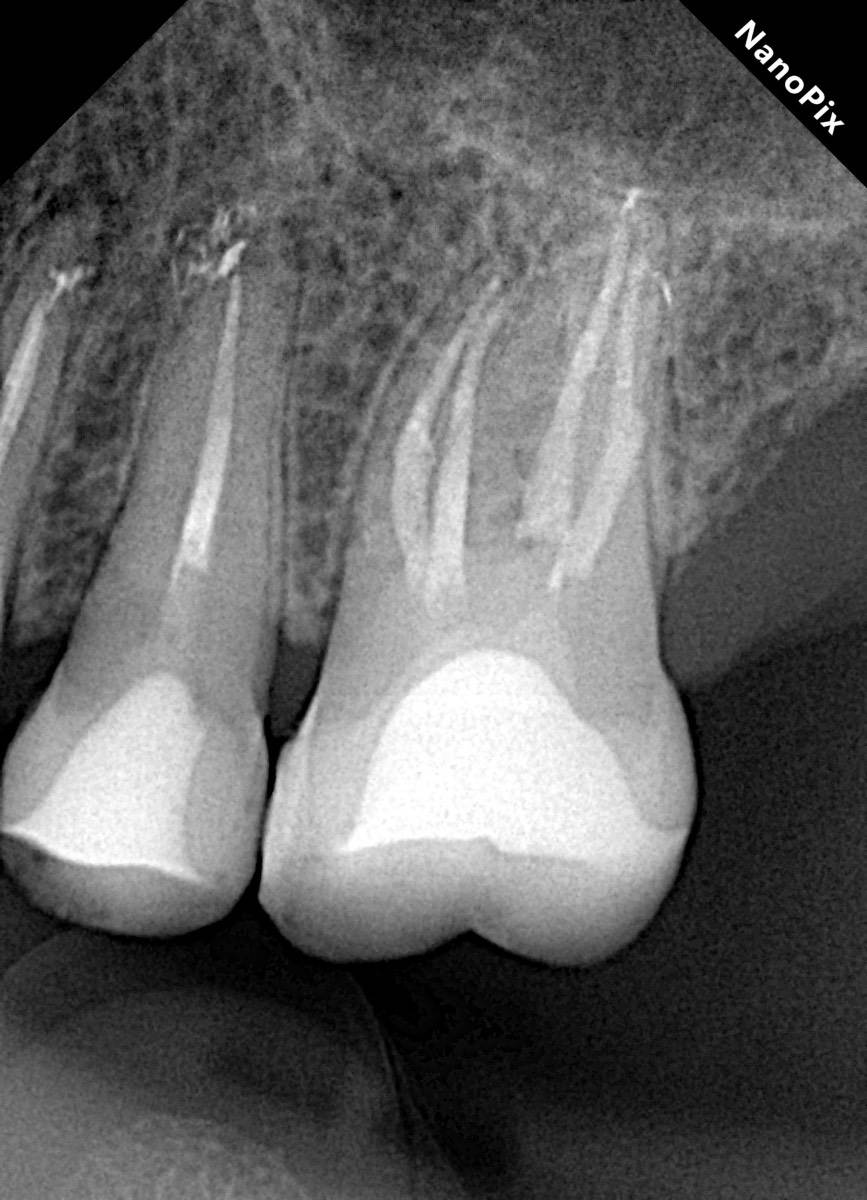

Гарриевич Опубликовано 3 апреля Автор Поделиться Опубликовано 3 апреля Еще один осмотр спустя 3 года и полное заживление 2 1 Ссылка на комментарий

Гарриевич Опубликовано 7 апреля Автор Поделиться Опубликовано 7 апреля Извлечение двух фрагментов сломанных инструментов из одного зуба:) И если кому интересно, то вот полный фотопротокол 3 Ссылка на комментарий